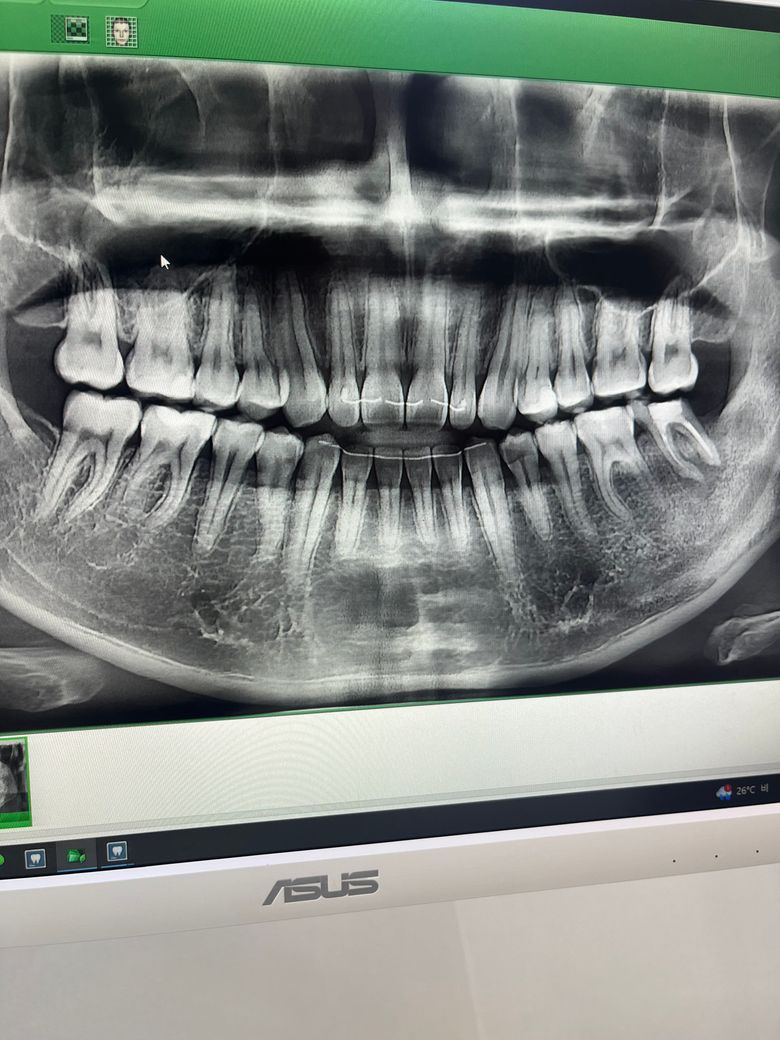

10년전쯤 신경치료한 치아가 있는데 뿌리끝 염증이 심해서 발치를 할 것 같아요. 근데 제가 신경치료할 때도 마취가 잘 안되서 엄청 아팠었거든요. 턱이 두꺼워서인지 아니면 염증때문이었는지는 모르겠어요. 근데 이번에도 지금 염증이 심한데 마취가 잘 될까 모르겠네요. 많이 아플까요ㅠㅠ

사진상 오른쪽 맨끝 아래 치아입니다

염증이 있는 상태에서 치아를 발치하는 것은 어느정도의 통증이나 불편감이 있을 수 밖에 없습니다. 다만 마취만 잘된다면 발치하는데 있어 극심한 통증까지는 이어지지 않습니다. 현재 사진으로 보아서는 신경치료한 치아는 더 이상 사용할 수 없고 발치해야할 것으로 보입니다.